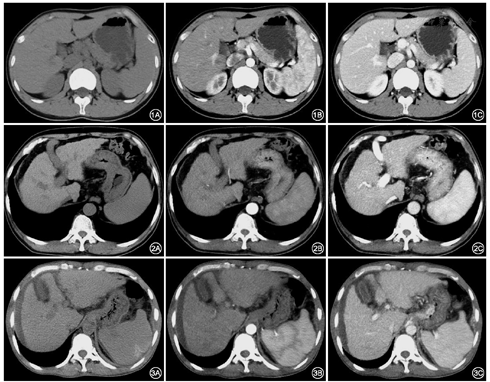

两名医师主观评分一致性较高(kappa=0.79~0.86)。平扫和动脉期,试验组和对照组图像的主观评分无明显变化(P>0.05)(表6)(图1,图2)。门脉期Child-Pugh C级组较其余3组评分减低,均值<3分,影响诊断,且与其余3组差异均有统计学意义(Z=26.734~29.218,均P< 0.05)(图3)。

本研究将前置ASIR-V比例按不同期相自30%~50%分组,可以进行组间和组内对比。结果显示同一期相肝硬化不同肝功能分级,辐射剂量较对照组下降;同一肝功能分级门脉期较动脉期及平扫辐射剂量亦减低,前置ASIR-V50%较对照组ED下降46.7%,此结果与柴亚如等[4]的结论接近。再次验证了前置ASIR-V可降低辐射剂量,且剂量降低的程度与其比值呈正比。但前置ASIR-V比值过高,空间分辨率下降,组织及脏器边缘锐利度降低,图像失真,出现水墨画样改变。本研究显示肝功能Child-Pugh A、B级随着前置ASIR-V比值的升高各脏器及血管的CNR值无明显变化,但Child-Pugh C级前置ASIR-V50%时肝脏、门静脉的CNR值减低,且门脉期图像实质脏器颗粒增粗,空间分辨力和组织间对比度下降,部分患者主观评分<3,影响诊断。这可能因肝硬化患者当肝功能明显减低及门脉高压合并大量侧支循环开放时,门-腔分流,进入肝脏的血液减少,肝脏及门脉的CT值减低;且患者常伴有大量腹水、腹壁水肿,其BMI值较高等均影像图像质量[11,12],此时对于肝功能Child-Pugh C级的患者前置ASIR-V推荐40%。